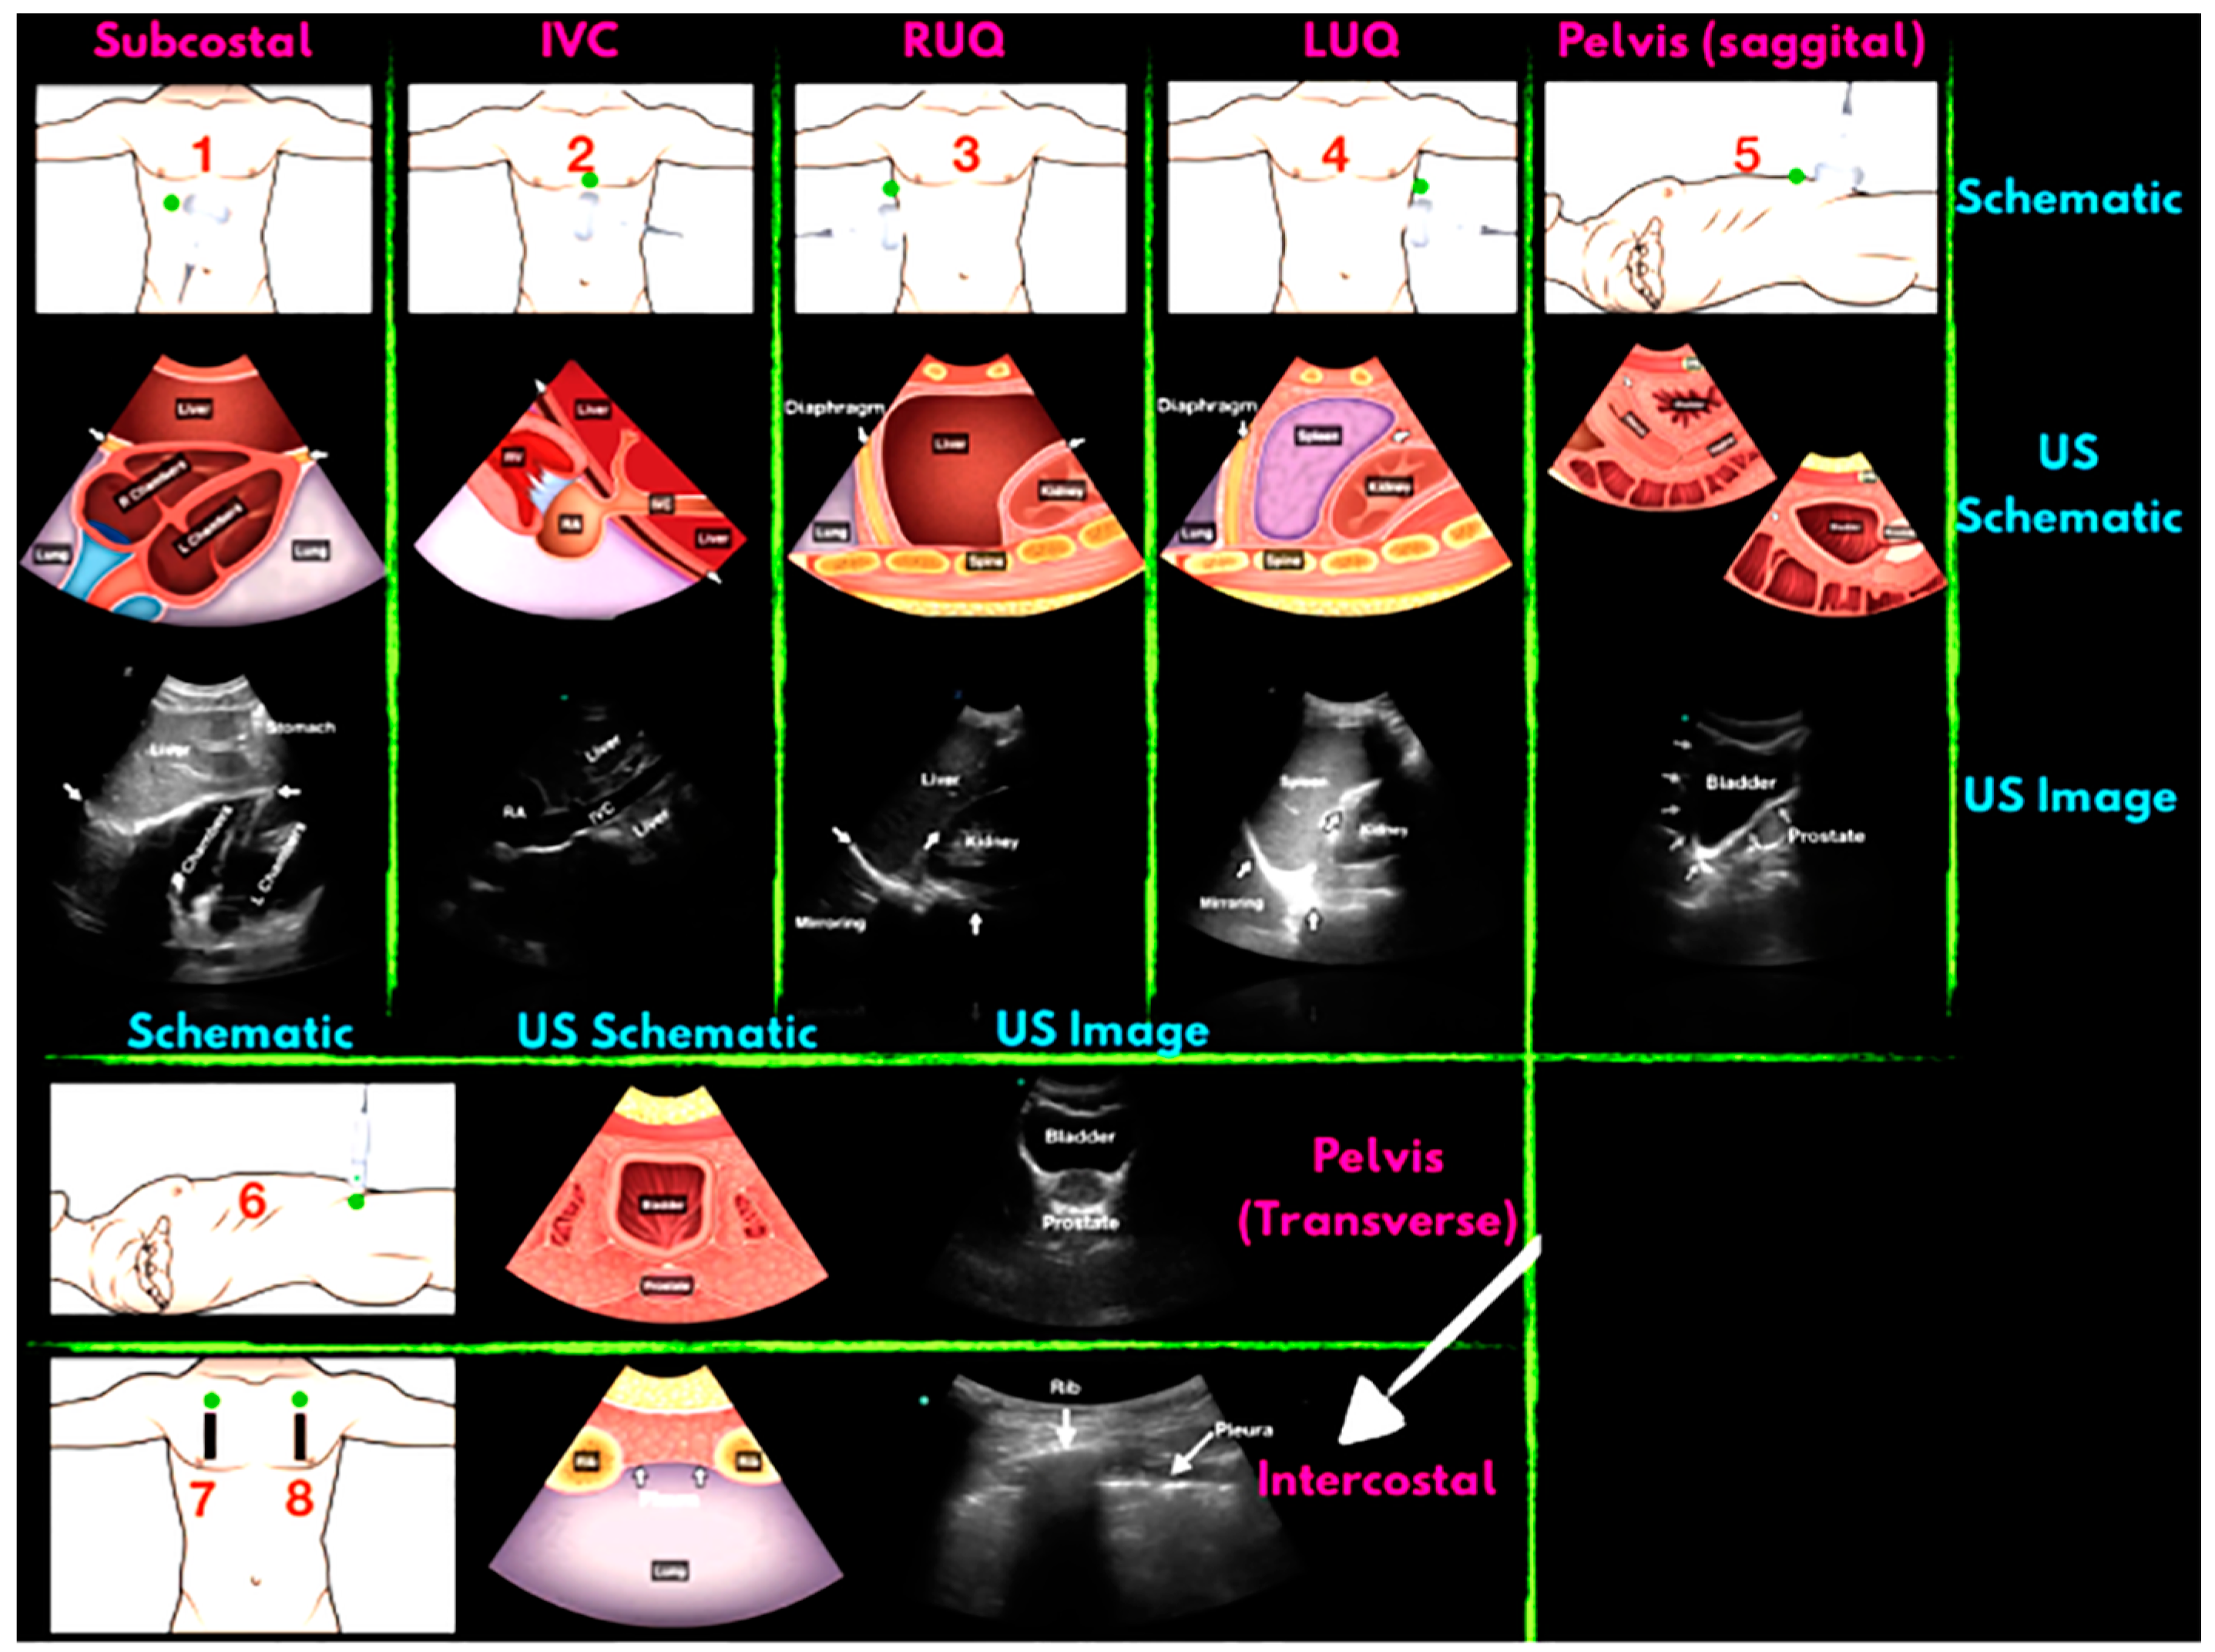

2.2. Application of Portable Intelligent Ultrasound in the Diagnosis of Abdominal Trauma

- Gleeson, T.; Blehar, D. Point-of-care ultrasound in trauma. Semin. Ultrasound CT MRI 2018, 39, 374–383. [Google Scholar] [CrossRef]

- Stawicki, S.P.; Howard, J.M.; Pryor, J.P.; Bahner, D.P.; Whitmill, M.L.; Dean, A.J. Portable ultrasonography in mass casualty incidents: The CAVEAT examination. World J. Orthop. 2010, 1, 10–19. [Google Scholar] [CrossRef]